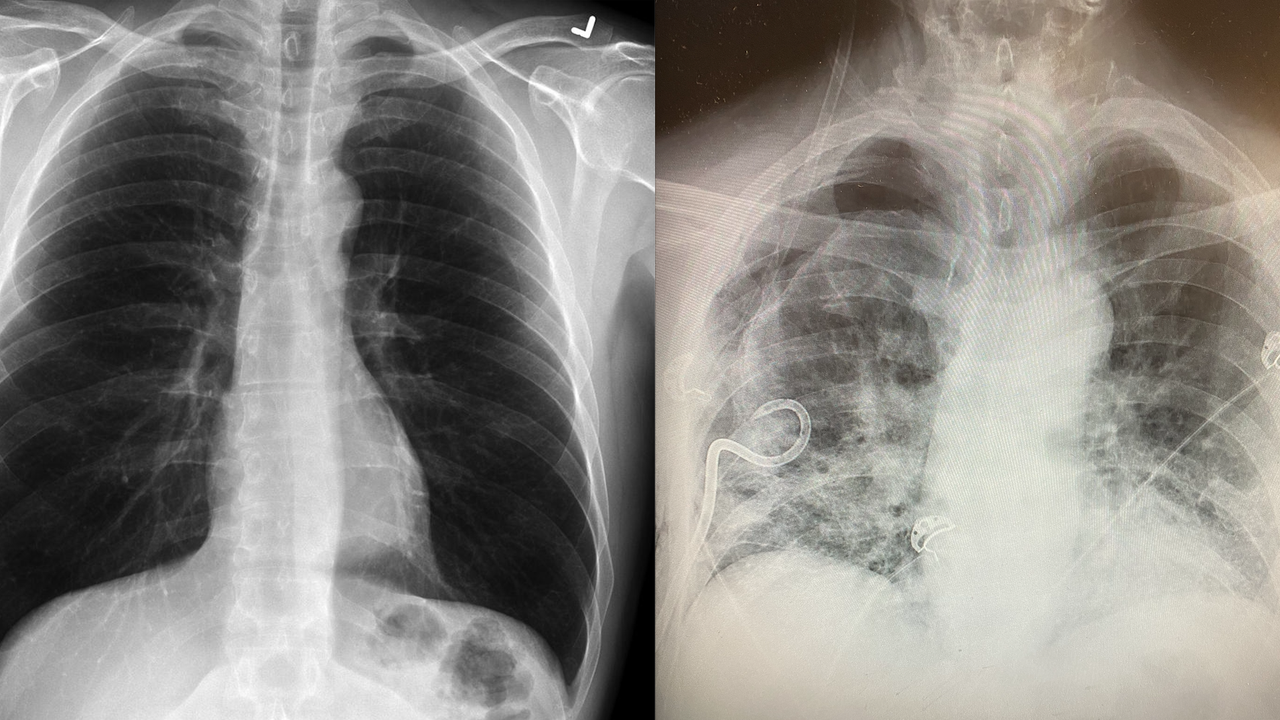

A normal, healthy lung compared to a post-COVID lung. (Credit: Dr. Brittany Bankhead-Kendall)

A Texas doctor is noticing a pattern in her patients that could reveal another possible devastating side effect of COVID-19: severely scarred lungs.

Dr. Brittany Bankhead-Kendall, a trauma surgeon at Texas Tech University Health Sciences Center, said she’s seeing lung scarring in some patients who have had COVID-19 that’s worse than what she sees in the lungs of people who smoke. She said she’s noticed the lung scarring in X-rays she’s taken for subsequent, unrelated health issues.

"It looks like a lot of dense scarred tissue and that extends throughout the entire lung," she explained. "Additionally, we’re seeing signs of congestion and fibrosis."